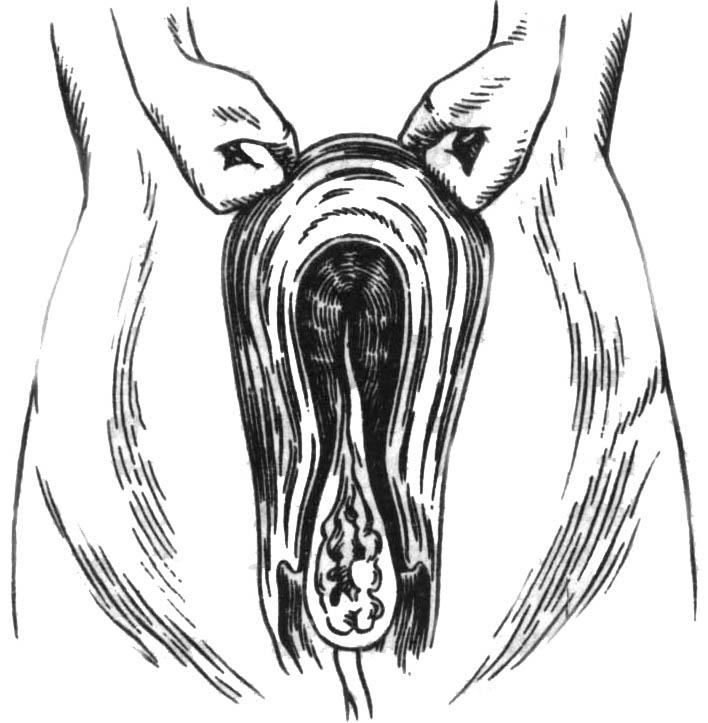

Медицинская визуализация: Признак Кюстнера-Чукалова

Раздел: Необычные решения